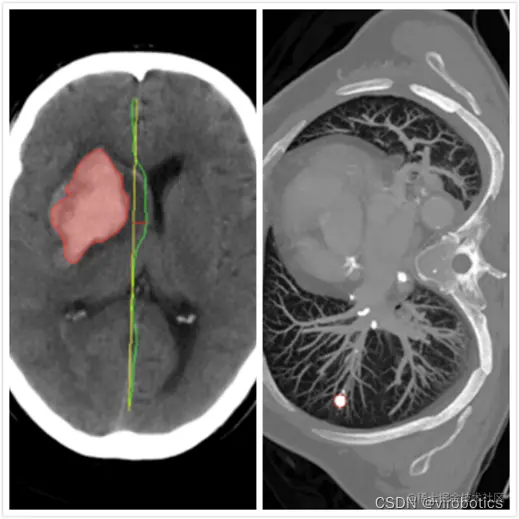

随着人工智能的崛起,将神经网络与医疗诊断结合也成为研究热点,智能医疗研究逐渐成熟。在智能医疗领域,语义分割主要应用于肿瘤图像分割,龋齿诊断等。(下图分别是龋齿诊断,头部CT扫描紧急护理诊断辅助和肺癌诊断辅助) 在这里插入图片描述 在这里插入图片描述